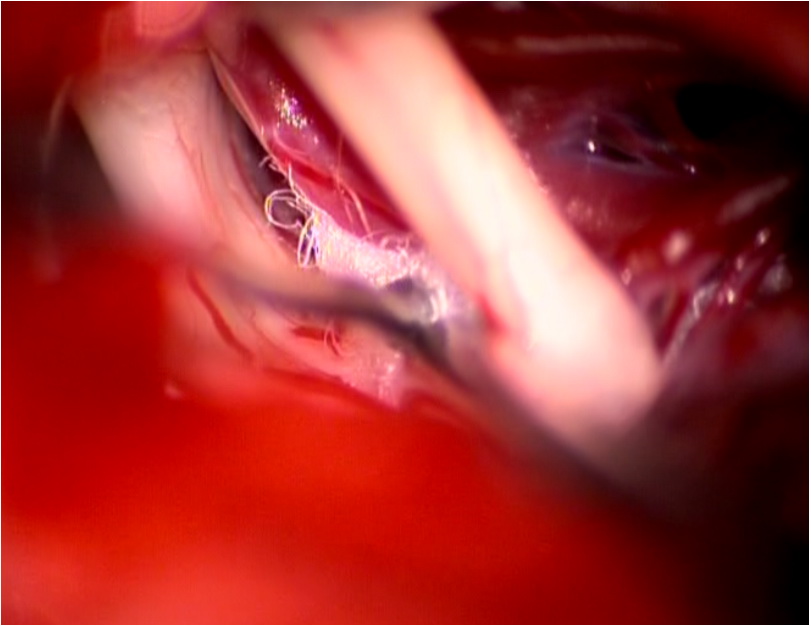

三叉神经微血管减压手术切口

术中显微镜镜下神经显露